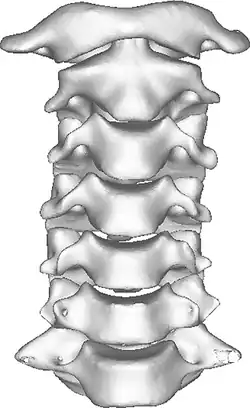

Once there is an onset of the symptoms in the patient, the patients are screened through cervical-spinal imaging techniques: X-ray, CT, MRI. [1] The scanning technique points out any cervical vertebrae defects and misalignments. (Image 1. and 2.) When cervicocranial syndrome is caused as a result of a genetic disease, then family history and genetic testing aid in making an accurate diagnosis of cervicocranial syndrome.